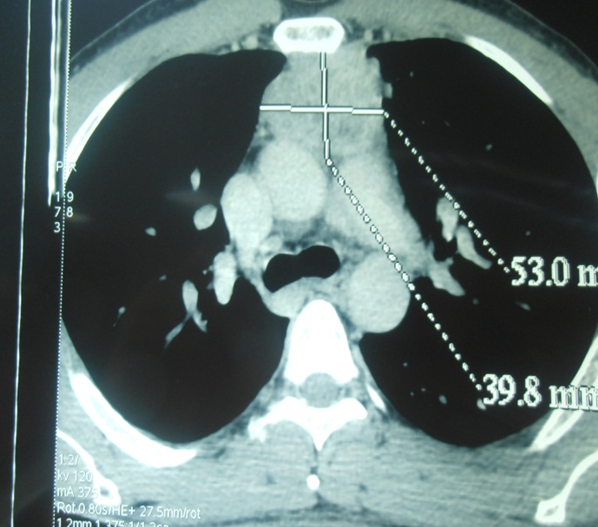

Les thymomes sont des tumeurs épithéliales rares chez l'adulte. Ils se manifestent le plus souvent par une douleur thoracique, une dyspnée ou un syndrome cave supérieur associés ou non à une myasthénie. La rareté et la diversité de la présentation clinique rend le diagnostic positif des thymomes difficile. Patient âgé de 40 ans, tabagique, qui a consulté pour une dysphonie chronique évoluant depuis 3 mois, qui s'est exacerbée depuis 15 jours sans dyspnée ni dysphagie. L'examen cervical trouvait une loge thyroïdienne et des aires ganglionnaires libres. La nasofibroscopie a révélé une corde vocale gauche immobile en position paramédiane. En laryngoscopie directe, l'endolarynx était d'aspect normal. La Radiographie du thorax était sans anomalies. Le bilan biologique était normal. La TDM thoracique a objectivé un processus tissulaire médiastinal supérieur, de rehaussement intense et hétérogène, mesurant 9 x 5 cm, arrivant en bas jusqu'au toit de la crosse de l'aorte. Le patient a été opéré en chirurgie thoracique par voie de sternotomie et a eu une exérèse totale de la masse. Celle-ci présentait des adhérences avec le nerf récurrent gauche sans l'envahir. Les suites post-opératoires étaient simples. L'examen anatomopathologique a conclut à un thymome encapsulé sans signes histologiques de malignité. L'évolution était marquée par une amélioration de la dysphonie.